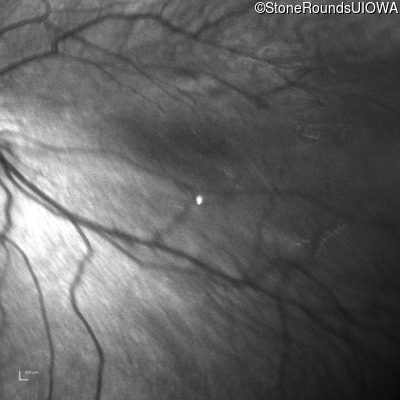

Infrared Fundus Photograph - Left - 20/80

Exemplar